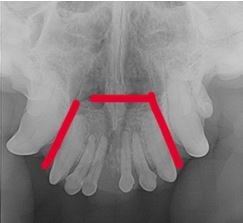

De gouden standaard voor beeldvorming bij tumoren in de mondholte is doorgaans CT, maar aangezien het om een ameloblastoom gaat en we weten dat het enkel lokaal invasief groeit, was dentale radiografie in dit geval voldoende.

We planden voor Rosa een premaxillectomie in, waarbij we een resectie doen van beide os incisivi inclusief alle omgevende weke delen/structuren (en block excisie).